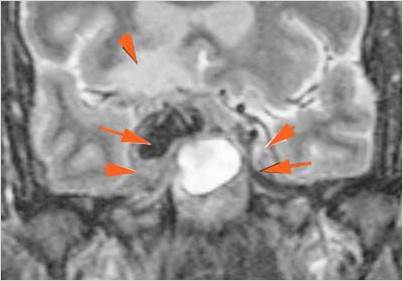

There is brain edema specifically involving the frontal and temporal lobes. |

Yes | NA |

There is cerebritis specifically involving the frontal and temporal lobes. |

Findings are consistent with the clinical diagnosis of acute or subacute sinusitis superimposed on chronic mucocele with intracranial complications of epidural empyema along the orbital roof and early frontal lobe cerebritis.